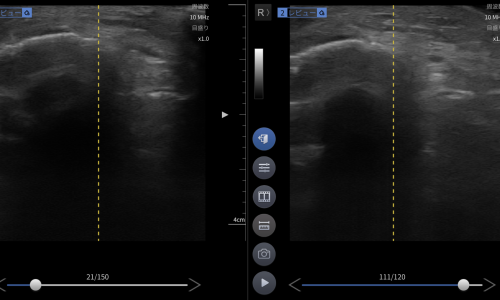

臨床的に高齢者の転倒による膝強打では膝蓋骨骨折を強く疑う所見。エコーで関節内血腫を確認し、膝蓋骨に骨折様所見を認め、膝蓋骨骨折および関節内損傷を疑い整形外科へ紹介しました。

- エコーで骨癒合良好